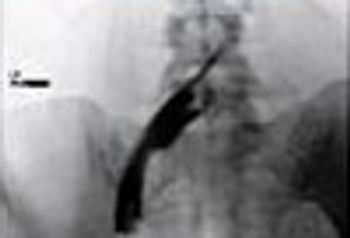

Also known as “broken-heart syndrome,” Takotsubo syndrome is a stress-induced cardiomyopathy.